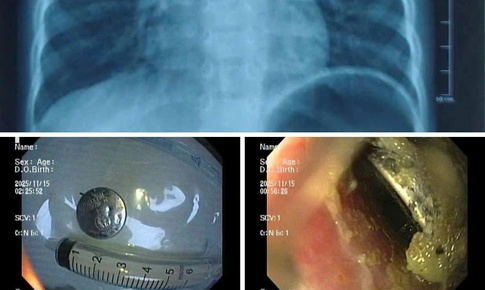

loét thực quản

Tra cứu bệnh - 22/04/2025 15:00SKĐS - Loét thực quản là một trong những biến chứng phổ biến của trào ngược dạ dày - thực quản, gây đau rát vùng ngực, khó nuốt, thậm chí ảnh hưởng đến chất lượng sống.